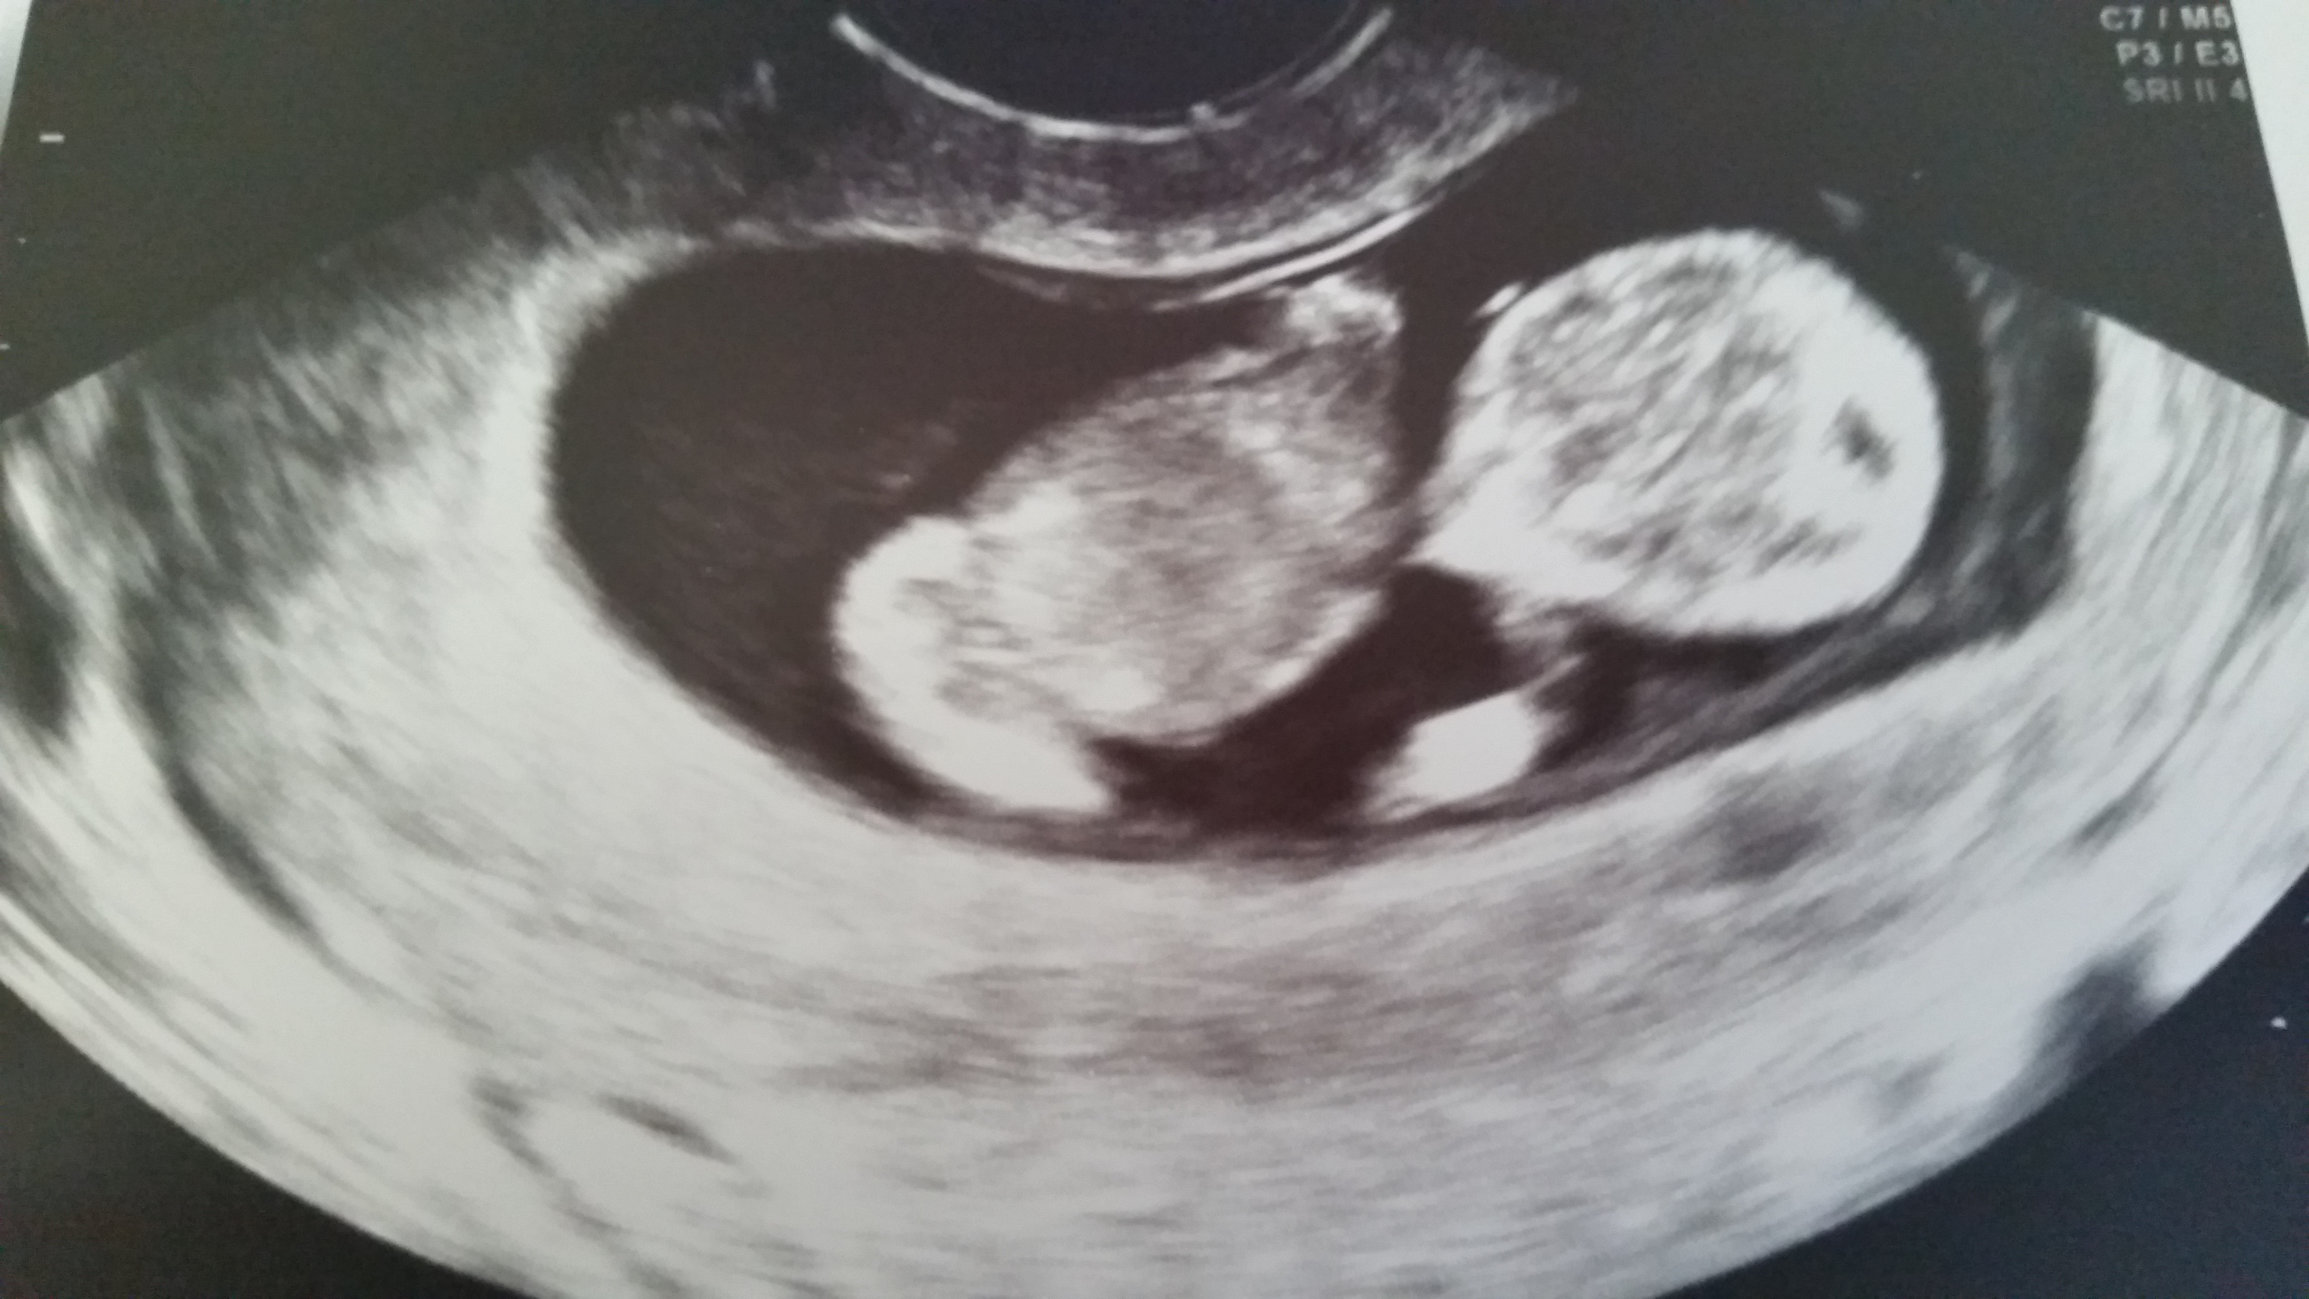

My 8 week ultrasound pic from last week - my husband and I found out we’re having twins! Di dizygotic twins, so they will most likely be fraternal but if they are the same sex we won’t know for sure if they are identical until they are born. Right now they are both looking healthy and have strong little heartbeats of 155 and 169 bpm. Can’t wait to continue watching them grow!